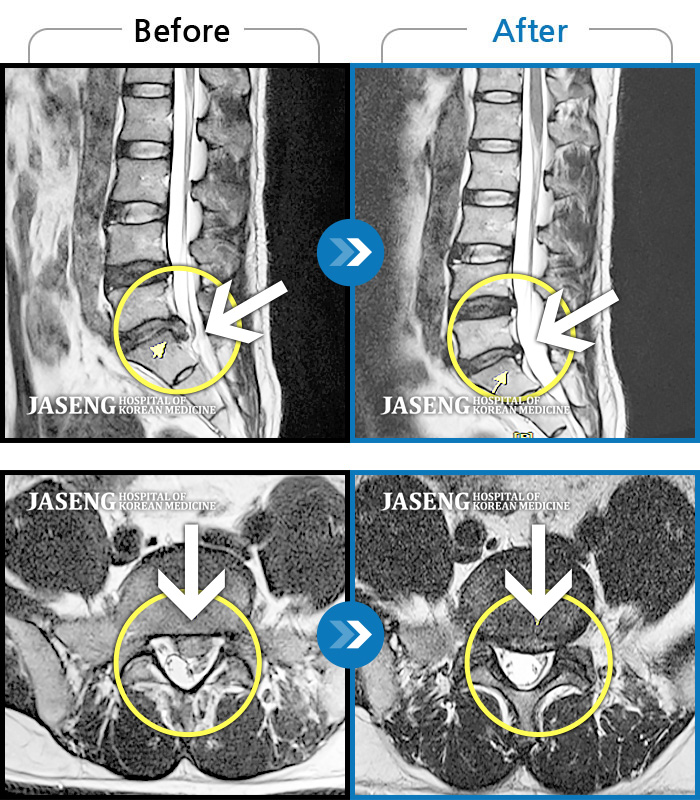

허리디스크

광주 · 김준수 원장

양측 허리에 묵직한 통증과 양측 허벅지부터 종아리까지 하지 방사통

촬영시기

2022.06.21 ~ 2022.12.24

2022.12.29

조회수 208